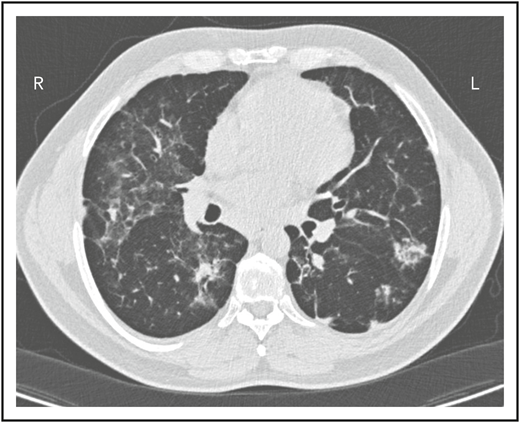

A second common reason for a patient to come to the attention of hematologists is the finding of an enlarged spleen, especially in an adult with lymphadenopathy. This was the reason in patient 2, who is now a 46-year-old male professional dog walker. At the age of 31, he was found to have an enlarged spleen together with cervical and axillary lymphadenopathy. Hematology was consulted, and the lymph node was biopsied; pathology revealed that he had noncaseating granuloma. He was then referred to pulmonology and, with this evidence, was diagnosed with sarcoidosis and treated with steroids for some months, but he stopped the treatment. Although he had no obvious respiratory symptoms over the following 15 years, he had a slow decline in lung function, and chest computed tomography showed hilar lymphadenopathy, ground-glass opacities with nodules, and bronchiectatic changes (Figure 2). In 2018, he had acute bacterial pneumonia, became concerned, and found on the internet that granulomata in the lungs and an enlarged spleen might be related to low serum immunoglobulin levels. He asked that this be tested; when this test was performed, he had striking low serum immunoglobulins: IgG, 97 mg/dL; IgA, <5 mg/dL; IgM, 27 mg/dL. However, within the month, he was hospitalized for pneumonia due to metapneumovirus. The diagnosis of CVID was finally made, and immunoglobulin treatment was started. The patient’s spleen remains large.

The patient in clinical case 2 had a slow decline in lung function due to his immune defect, but this was assumed to be due to sarcoidosis. Chest computed tomography showed ground-glass opacities with numerous nodules, hilar lymphadenopathy, and bronchiectatic changes. With granuloma on biopsy, these changes were consistent with granulomatous lymphocytic interstitial lung disease.

Localized or systemic granulomatous disease, sometimes erroneously called “sarcoidosis,” occurs in between 8% and 22% of subjects with CVID.18,19 For unclear reasons, many of these patients have also had ITP or AIHA. In the patient in clinical case 2, although he did not have characteristic lung infections such as pneumonia for many years, the diagnosis of “sarcoid” retarded the recognition of the underlying immune defect; this confusion has repeatedly been observed, and the delay in diagnosis can be for more than a decade, as it was in this case.19 Organisms must be sought but are very rarely found. In CVID, the granulomatous changes are usually found in lungs, lymph nodes, or spleen, but the skin, liver, bone marrow, kidney, gastrointestinal tract, and brain can also be involved. In the lungs, an intense lymphoid infiltration accompanies the granulomas, leading to what is termed “granulomatous lymphocytic interstitial lung disease.”18 For unclear reasons, patients with granulomatous disease are likelier to have ITP or AIHA than those with CVID, who do not have this pathology and thus require the attention of hematologists.